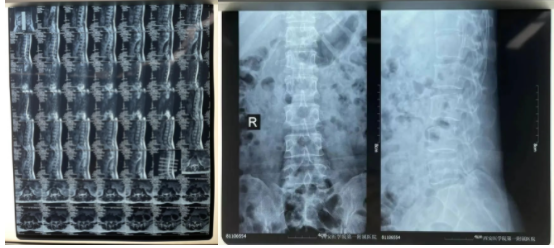

患者术前影像资料(腰5骶1节段腰椎间盘突出)